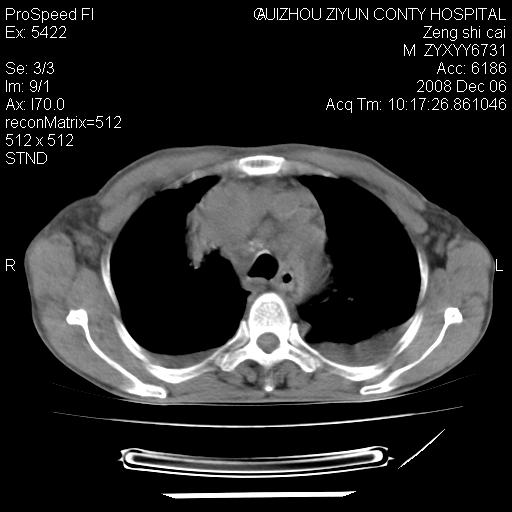

标题: CT16961:M、71岁,咳嗽半年,无血痰;胸片示右肺占位。 [打印本页]

标题: CT16961:M、71岁,咳嗽半年,无血痰;胸片示右肺占位。

右肺癌并纵隔淋巴结及胸膜转移可能性大

右肺癌并纵隔淋巴结及胸膜转移。建议气管镜

右肺纵隔型肺癌伴纵隔淋巴结及胸膜转移!

右肺纵隔型肺癌伴纵隔淋巴结转移!双侧胸水!

1)考虑右肺上叶纵隔型肺癌伴纵隔淋巴结转移。2)心包积液,双侧胸腔积液。

右肺癌并纵隔淋巴转移,腹膜后转移可能性大,两侧胸腔积液

右肺上叶纵隔型肺癌伴纵隔淋巴结转移。心包积液,双侧胸腔积液。

建议强化!主要鉴别是淋巴瘤与肺癌淋巴结转移。